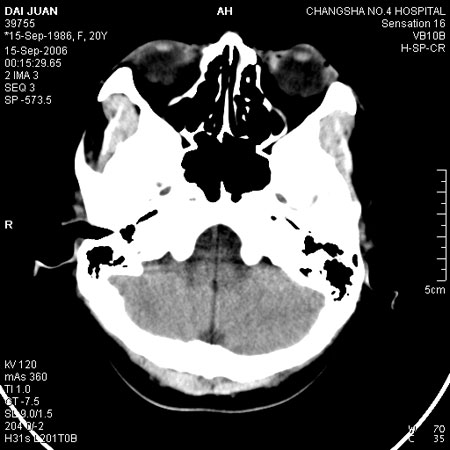

请问各位战友:图示箭头处是否为颅骨骨折?

病史:患者,女,20岁.头部及腹部外伤20分钟.伤后昏迷,无呕吐.头及右侧腰背部疼痛,双侧瞳孔等大,

右肾区叩痛.其它无异常.患者家属否认原有外伤史.

请大家看看是否为颅骨骨折.还是正常变异,或为陈旧骨折.谢谢.

图片未上传完,所见图象示枕骨线样低密度影,边缘锐利,结合外伤史,伤后昏迷,骨折不能除外。

枕骨的线样低密度影锐利、清晰,但正好位于矢状缝的位置,局部无明显软组织肿块,相临及对冲部位脑实质亦无出血及挫裂伤表现。

单就这几层暂不考虑骨折,建议上传完整图片。

楼主所关心的另一个线样影应该是头颅矢状面略偏左,射线正好穿过所致,不需要考虑骨折。

枕部锐利透亮线,可以考虑枕骨骨折.

枕骨是单块的,矢状缝是在顶骨而不是在枕骨,枕骨后缘见线状低密度,边缘税利,考虑在骨折存在。

枕后部及左侧颞枕部边缘锐利的线样低密度影,局部软组织无异常,左侧乳突蜂房密度均匀,硬膜下及脑实质内未见出血灶,考虑为正常变异。

枕部锐利透亮线,可以考虑枕骨骨折.左侧枕颞缝。

枕部考虑骨折。一般的颅逢不会跨越板障,楼主所示枕骨断面两侧板障也不连续。